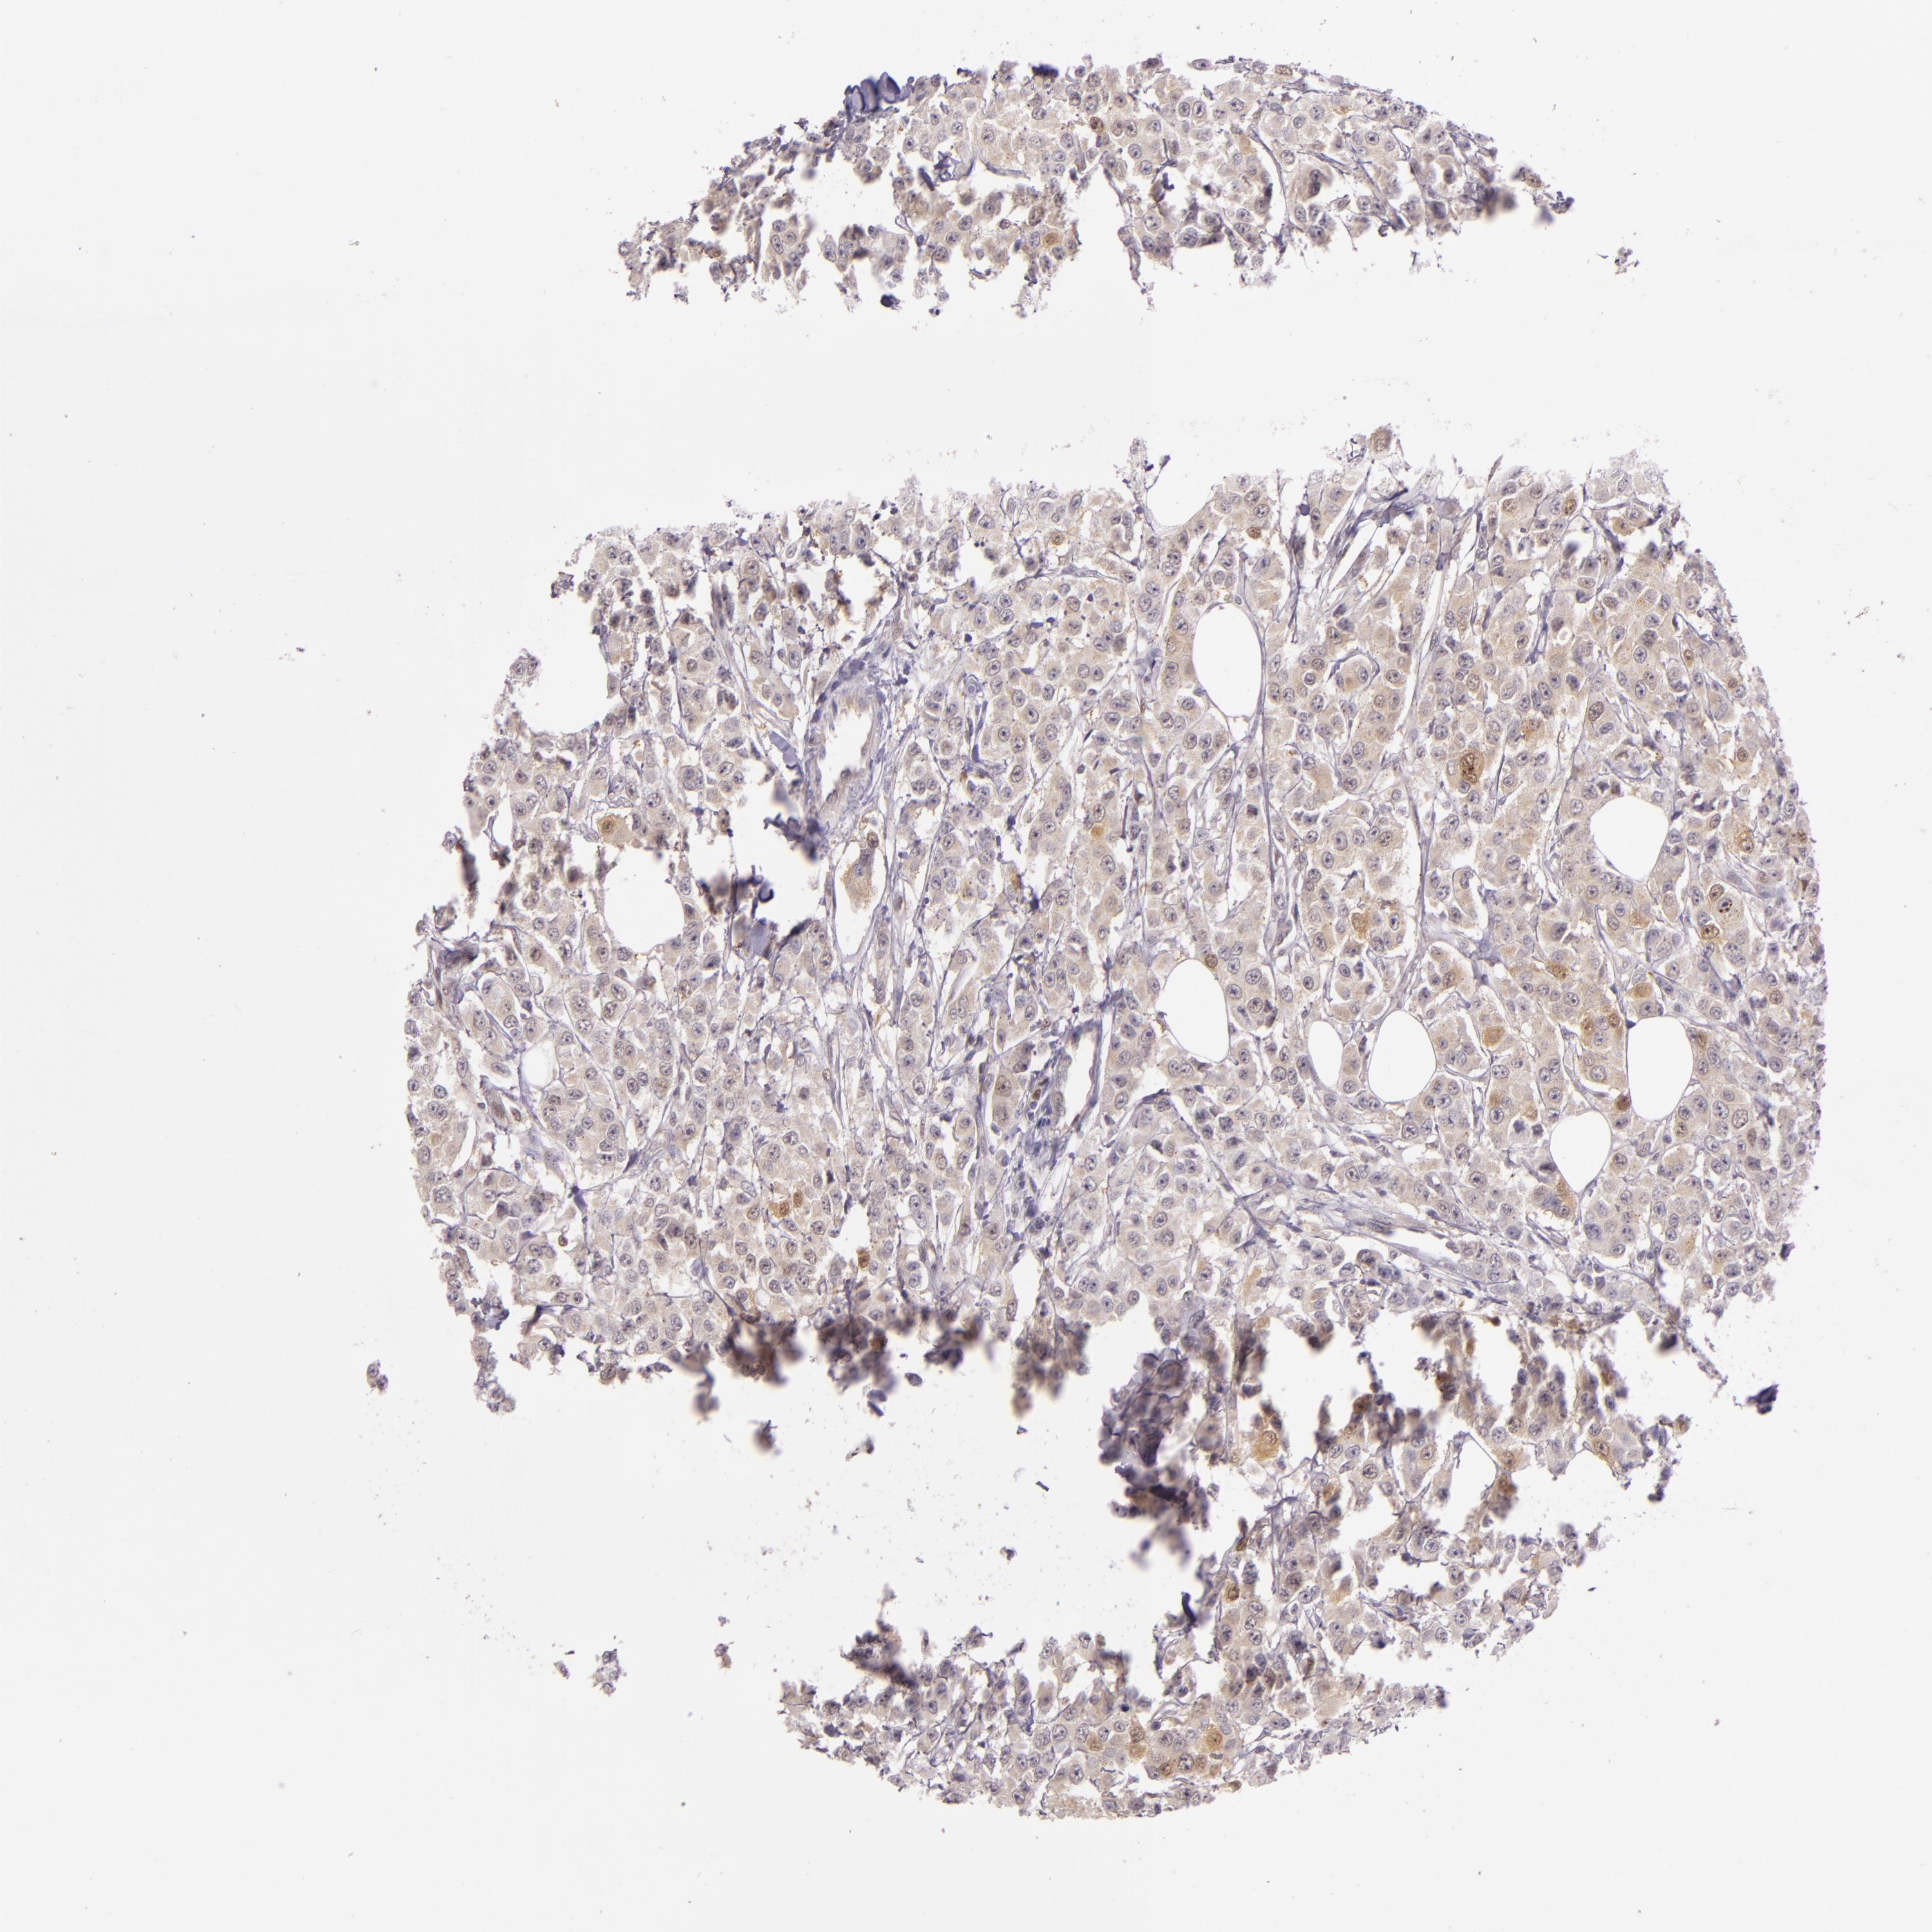

HSPA8

CANCER BREAST CANCER Show tissue menu

Breast cancer

Human cancer

HSPA8 is not prognostic in Breast Invasive Carcinoma (TCGA)